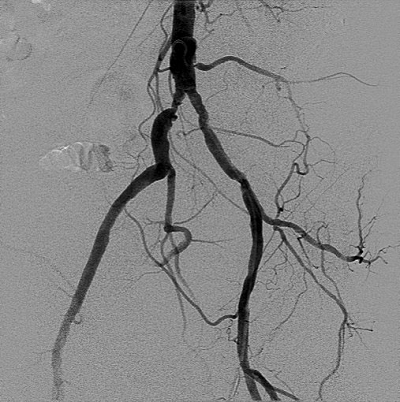

A 64-year-old man is evaluated in the office 7 days after discharge from the hospital for non–ST- elevation myocardial infarction. He was treated with percutaneous coronary intervention using a radial artery approach. Right femoral artery access was initially attempted, but the catheter guidewire could not be passed. During the procedure, an abdominal aortogram was obtained (shown). He has not had any symptoms of claudication. Medical history is significant for hyperlipidemia. He is a current smoker with a 40-pack-year history. Medications are low-dose aspirin, ticagrelor, metoprolol, and atorvastatin.

On physical examination, vital signs are stable. The right femoral pulse is faint, and a bruit is heard over the right femoral artery. No foot or toe ulceration is noted.

In this patient with asymptomatic peripheral artery disease (PAD) and acute coronary syndrome treated with percutaneous coronary intervention, the most appropriate next step in management is cardiac rehabilitation. Cardiac rehabilitation is indicated in all patients after hospitalization for acute coronary syndrome and percutaneous coronary intervention. In some patients, exercise can provoke symptoms of intermittent claudication; however, the presence of PAD is not a contraindication to cardiac rehabilitation.

This patient's iliac artery stenosis could be treated safely and effectively with an endovascular approach; however, endovascular treatment of PAD is not recommended in asymptomatic patients. There is no empiric evidence that endovascular intervention prevents disease progression to intermittent claudication or critical limb ischemia.

Asymptomatic lower extremity peripheral artery disease is managed with aggressive risk factor modification; cilostazol and surgical intervention do not affect progression of disease or prevent acute limb ischemia.